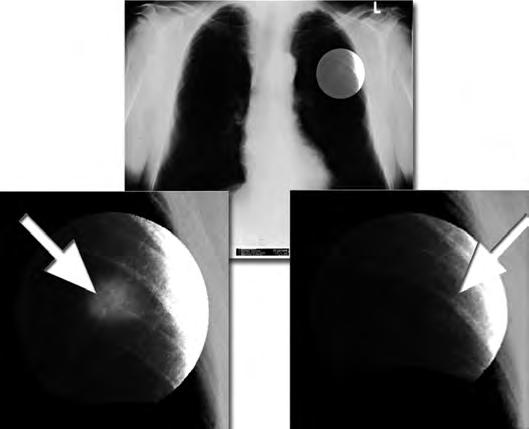

72 Zwycięstwo nad rakiem! Część 1: Niewyobrażalne stało się możliwe

Obszar wzrostu kości (epifiza)

Rak kości u dzieci

Rentgen raka kości: Rozwój raka w obszarze związanym

ze wzrostem tkanki kostnej, czyli blisko stawu kostnego.